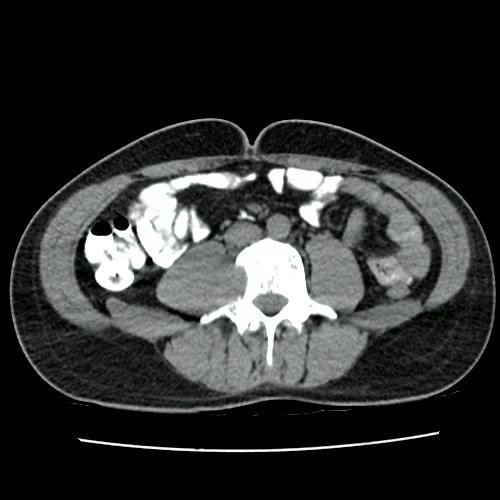

TAC de columna con contraste EV (Corte sagital y corte coronal): Presenta múltiples lesiones líticas óseas, bien circunscritas, que afectan en forma difusa todos los cuerpos vertebrales, sacro, pelvis ósea, esternón, clavícula y escápulas.además se desta